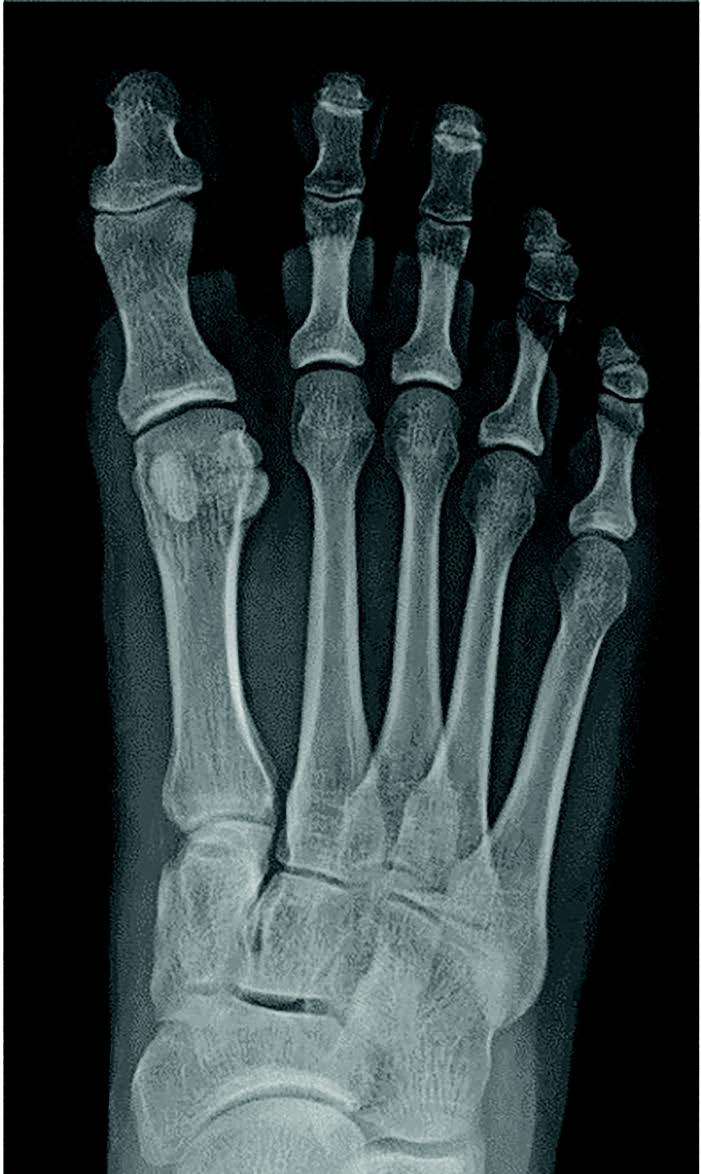

Typically, the hallux valgus angle is 5-15 degrees. In hallux varus, the angle is less than 5 degrees, and is most notably seen when less than 0 degrees. There is also a reduced intermetatarsal angle between the first and second metatarsals. Medial subluxation of the tibial sesamoid are also possible, as are degenerative changes at the MTPJ or IPJ. According to a 1997 article published by Alfred Philips, DPM, a negative PASA (proximal articular set angle) is present in untreated congenital hallux varus cases. This is occurs secondary to osseous adaptation to the tight abductor hallucis tendon.7

Within our database, to date, we have not seen a negative intermetatarsal angle in any idiopathic hallux varus case. We routinely see normal intermetatarsal angles and often see some greater than 10 degrees. We routinely see normal sesamoid positions. In our experience, the deformity is almost always a negative PASA deformity. For iatrogenic, it seems like everyone focuses on the sesamoids, but there can be multiple permutations of sesamoid shape, position, or even lack of sesamoids. I then wondered if metatarsal length played a role, but my archives show multiple cases with short and long first metatarsals (see images below). All have the same etiology, incongruent first MTPJ, and negative PASA.

Through the years of reviewing X-rays, we first look at the hallux abduction angle. When I see a rectus or adducted hallux, I will then use a digital measuring tool to measure, PASA, DASA, hallux abductus, and IM angles. Over the years, cataloging these deformities has become easier thanks to the Agfa Healthcare IMPAX DICOM system that we can use at Ft. Bragg and Ft. Leonard Wood.